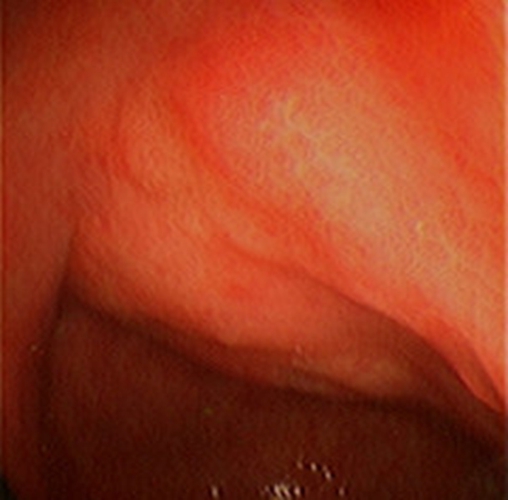

急性胃炎圖片

急性胃炎